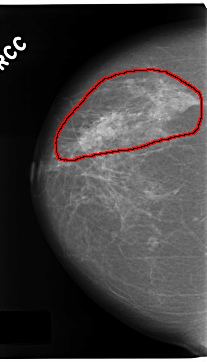

ics_version 1.0 filename C-0172-1 DATE_OF_STUDY 8 5 1996 PATIENT_AGE 70 FILM FILM_TYPE REGULAR DENSITY 2 DATE_DIGITIZED 12 3 1998 DIGITIZER LUMISYS LASER SEQUENCE LEFT_CC LINES 4760 PIXELS_PER_LINE 2616 BITS_PER_PIXEL 12 RESOLUTION 50 NON_OVERLAY LEFT_MLO LINES 4720 PIXELS_PER_LINE 2816 BITS_PER_PIXEL 12 RESOLUTION 50 NON_OVERLAY RIGHT_CC LINES 4696 PIXELS_PER_LINE 2680 BITS_PER_PIXEL 12 RESOLUTION 50 OVERLAY RIGHT_MLO LINES 4640 PIXELS_PER_LINE 2976 BITS_PER_PIXEL 12 RESOLUTION 50 OVERLAY |

FILE: C_0172_1.RIGHT_CC.OVERLAY TOTAL_ABNORMALITIES 1 ABNORMALITY 1 LESION_TYPE CALCIFICATION TYPE PLEOMORPHIC DISTRIBUTION REGIONAL ASSESSMENT 5 SUBTLETY 5 PATHOLOGY MALIGNANT TOTAL_OUTLINES 1 BOUNDARY |